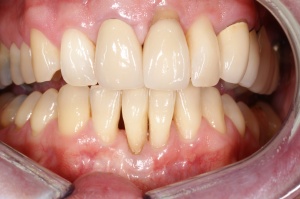

Aufgrund der parodontalen Destruktion, die letztlich erst mit dem intraoperativen Befund dreidimensional beurteilt werden konnte, mussten die Zähne 17, 26 und 27 als langfristig nicht erhaltungswürdig beurteilt werden. Da mit ihrem Verlust auch keine ausreichenden natürlichen Pfeiler mehr für einen definitiven festsitzenden Zahnersatz zur Verfügung standen, wurde eine implantatprothetische Versorgung mit zwei Implantaten in regio 15, 16 und drei Implantaten in regio 24, 25, und 26 geplant. Die Implantation und die entsprechenden präimplantologisch-augmentativen Maßnahmen wurde in der kieferchirurgischen Ambulanz (FU VIIb, Leiter Prof. Dr. Dr. K.O. Henkel) durchgeführt. Eine zwingende Indikation zur Versorgung der Freiendsituation ab 36 und der Schaltlücke bestand nicht, sodass in Übereinstimmung mit dem Patienten für den Unterkiefer kein Zahnersatz geplant und angefertigt wurde. Nach Wiedervorstellung im Oktober 2003 wurde die implantatprothetische Versorgung mit der Eingliederung der implantatgetragenen Kronen 15, 16, 24, 25, und 26 im November 2003 abgeschlossen. Mit der Eingliederung von Einzelkronen an 14, 13 und 23 im Februar 2004 wurde die Behandlung insgesamt abgeschlossen (s. Abb. 6). Die ursprünglich angedachte Extraktion der Molaren 17 und 28 wollte der Patient nicht mehr durchführen lassen.

Ab dem Februar 2004 wurde der Patient zur Sicherung des Behandlungserfolges in das in der FU VIIa – Zahnmedizin seit 1996 praktizierte Recallsystem aufgenommen. Diese Erhaltungstherapie beinhaltet die bereits erwähnten Maßnahmen der Unterstützenden Parodontitistherapie (UPT). Aufgrund dienstlicher Erfordernisse (u. a. immer wieder Seefahrten des Patienten) konnte der zunächst geplante Abstand von vier Monaten nicht immer eingehalten werden. Ein Abstand von ca. sechs Monaten konnte jedoch trotz der teilweise schwierigen Rahmenbedingungen realisiert werden. Am Zahn 44 kam es im Jahr 2006 zu einem Rezidiv, sodass an diesem Zahn im September 2006 eine Lappenoperation durchgeführt wurde. Der intraoperativ vorgefundene tiefe cirkuläre vertikale Defekt führte zur Einschätzung einer langfristig fraglichen Prognose von 44. Im Zuge der weiteren Erhaltungstherapie zeigten sich bis auf 44 die parodontalen und periimplantären Gewebe völlig unauffällig: So betrugen die Sondiertiefen bei entzündungsfreien klinischen Verhältnissen durchweg zwei bis drei Millimeter. Auch radiologisch zeigten sich keine Auffälligkeiten. Es gab keine Progredienz der ehemaligen parodontalen Erkrankung, die Osseointegration der Implantate zeigte keine Veränderungen (s. Abb. 7). Erhöhte Sondiertiefen verblieben lediglich am Zahn 44. Nachdem sich trotz regelmäßiger Nachsorge an 44 keine Entzündungsfreiheit der marginalen Gingiva erzielen ließ und die Zahnlockerung von 44 zunehmend stärker wurde, erfolgte im Jahre 2010 die Entfernung des Zahnes und der Ersatz durch eine implantatgetragene Krone (s. Abb. 8). Die Erhaltungstherapie wurde fortgeführt, Behandlungsmaßnahmen über die Inhalte der UPT hinaus waren bis zur Entlassung des Soldaten im Jahre 2012 nicht erforderlich. Der Patient blieb jedoch auch nach der Entlassung aus dem aktiven Dienst Patient des Hauses, sodass die Erhaltungstherapie in der FU VIIa – Zahnmedizin fortgeführt werden konnte. Im April 2013 stellte sich der Patient mit Beschwerden am Zahn 45 vor, der Zahn wies zudem eine Lockerung des Grades II auf. Die durchgeführte Röntgendiagnostik (s. Abb. 9) zeigte eine Wurzelfraktur im apikalen Wurzeldrittel, ein Zahnerhalt von 45 war nicht möglich und der Zahn wurde noch in gleicher Sitzung entfernt. Zur Versorgung der Lücke wären verschiedene prothetische Lösungen möglich gewesen. Letztlich fiel die Entscheidung zugunsten eine Extensionsbrücke von regio 45 auf 48. So konnte die Implantatkrone 44 belassen und mit dem Lückenschluss mittels einer vergleichsweise einfachen und schnellen prothetischen Versorgung auch die Schaltlücke 46 geschlossen werden. Der Patient befindet sich nach wie vor in der FU VIIa in der Erhaltungstherapie, die Fotos zeigen den aktuellen klinischen Befund in der Aufsicht des Ober- und Unterkiefers (s. Abb. 10, 11).